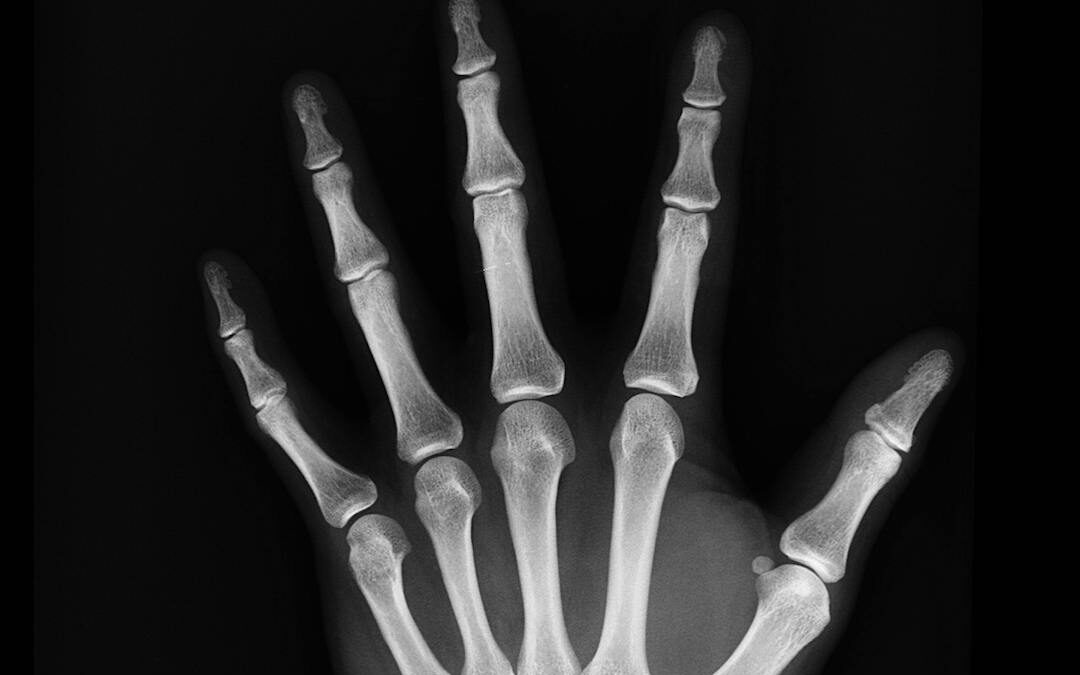

Relieving and Preventing Joint Pain

Movement can help us release stress, tension, and overcome stagnation in the mind and body. But when our habits of movement become aren’t a dynamic balance of muscle use or are too sedentary, it can lead to the development of joint pain and arthritis. Most...